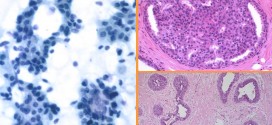

El adenocarcinoma de cuello uterino. El cuello del útero es la parte inferior del útero (la matriz). Algunas veces se le llama cuello uterino. El feto crece en el cuerpo del útero (la parte superior). El cuello uterino conecta el cuerpo del útero con la vagina (el canal por donde nace el bebé). La parte del cuello uterino más cercana …

El adenocarcinoma de cervix. Los virus del papiloma humano (VPH) de los tipos 16 y 18 son los principales tipos que se asocian al cáncer ginecológico y genital. A saber, sin olvidar a los demás. Tiene forma de pera invertida y está situado en la pelvis, entre el recto y la vejiga. Está formado por dos partes: la zona más inferior, …